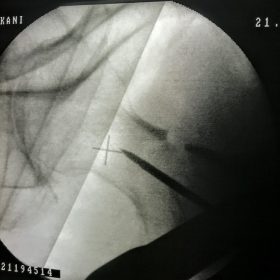

Υποκεφαλικό : Είναι ενδαρθρικό κάταγμα στον αυχένα του μηριαίου (το εσωτερικό του αρθρικού θυλάκου), το οποίο διακόπτει την αιμάτωση της κεφαλής του μηριαίου και οδηγεί σε μη πόρωση του κατάγματος (ΟΣΤΕΟΝΕΚΡΩΣΗ της Μηριαίας κεφαλής). Σε ασθενείς κάτω των 65 ετών αντιμετωπίζεται χειρουργικά με κοχλίωση στις πρώτες 12 ώρες. Τρείς βίδες σε σχήμα Τ με την βοήθεια τηλεόρασης διαδερμικά χωρίς διάνοιξη. Σε ασθενείς από 65-75 ετών γίνεται ολική αρθροπλαστική και σε ασθενείς άνω των 75 ετών αλλάζεται μόνο η κεφαλή χωρίς την αλλαγή της κοτύλης. Ο ασθενής περπατάει άμεσα μετεγχειρητικά στις 5 ώρες και εξέρχεται από το νοσοκομείο σε 1 -2 ημέρες. Στην κοχλίωση μπορεί να εξέλθει και την ίδια ημέρα.